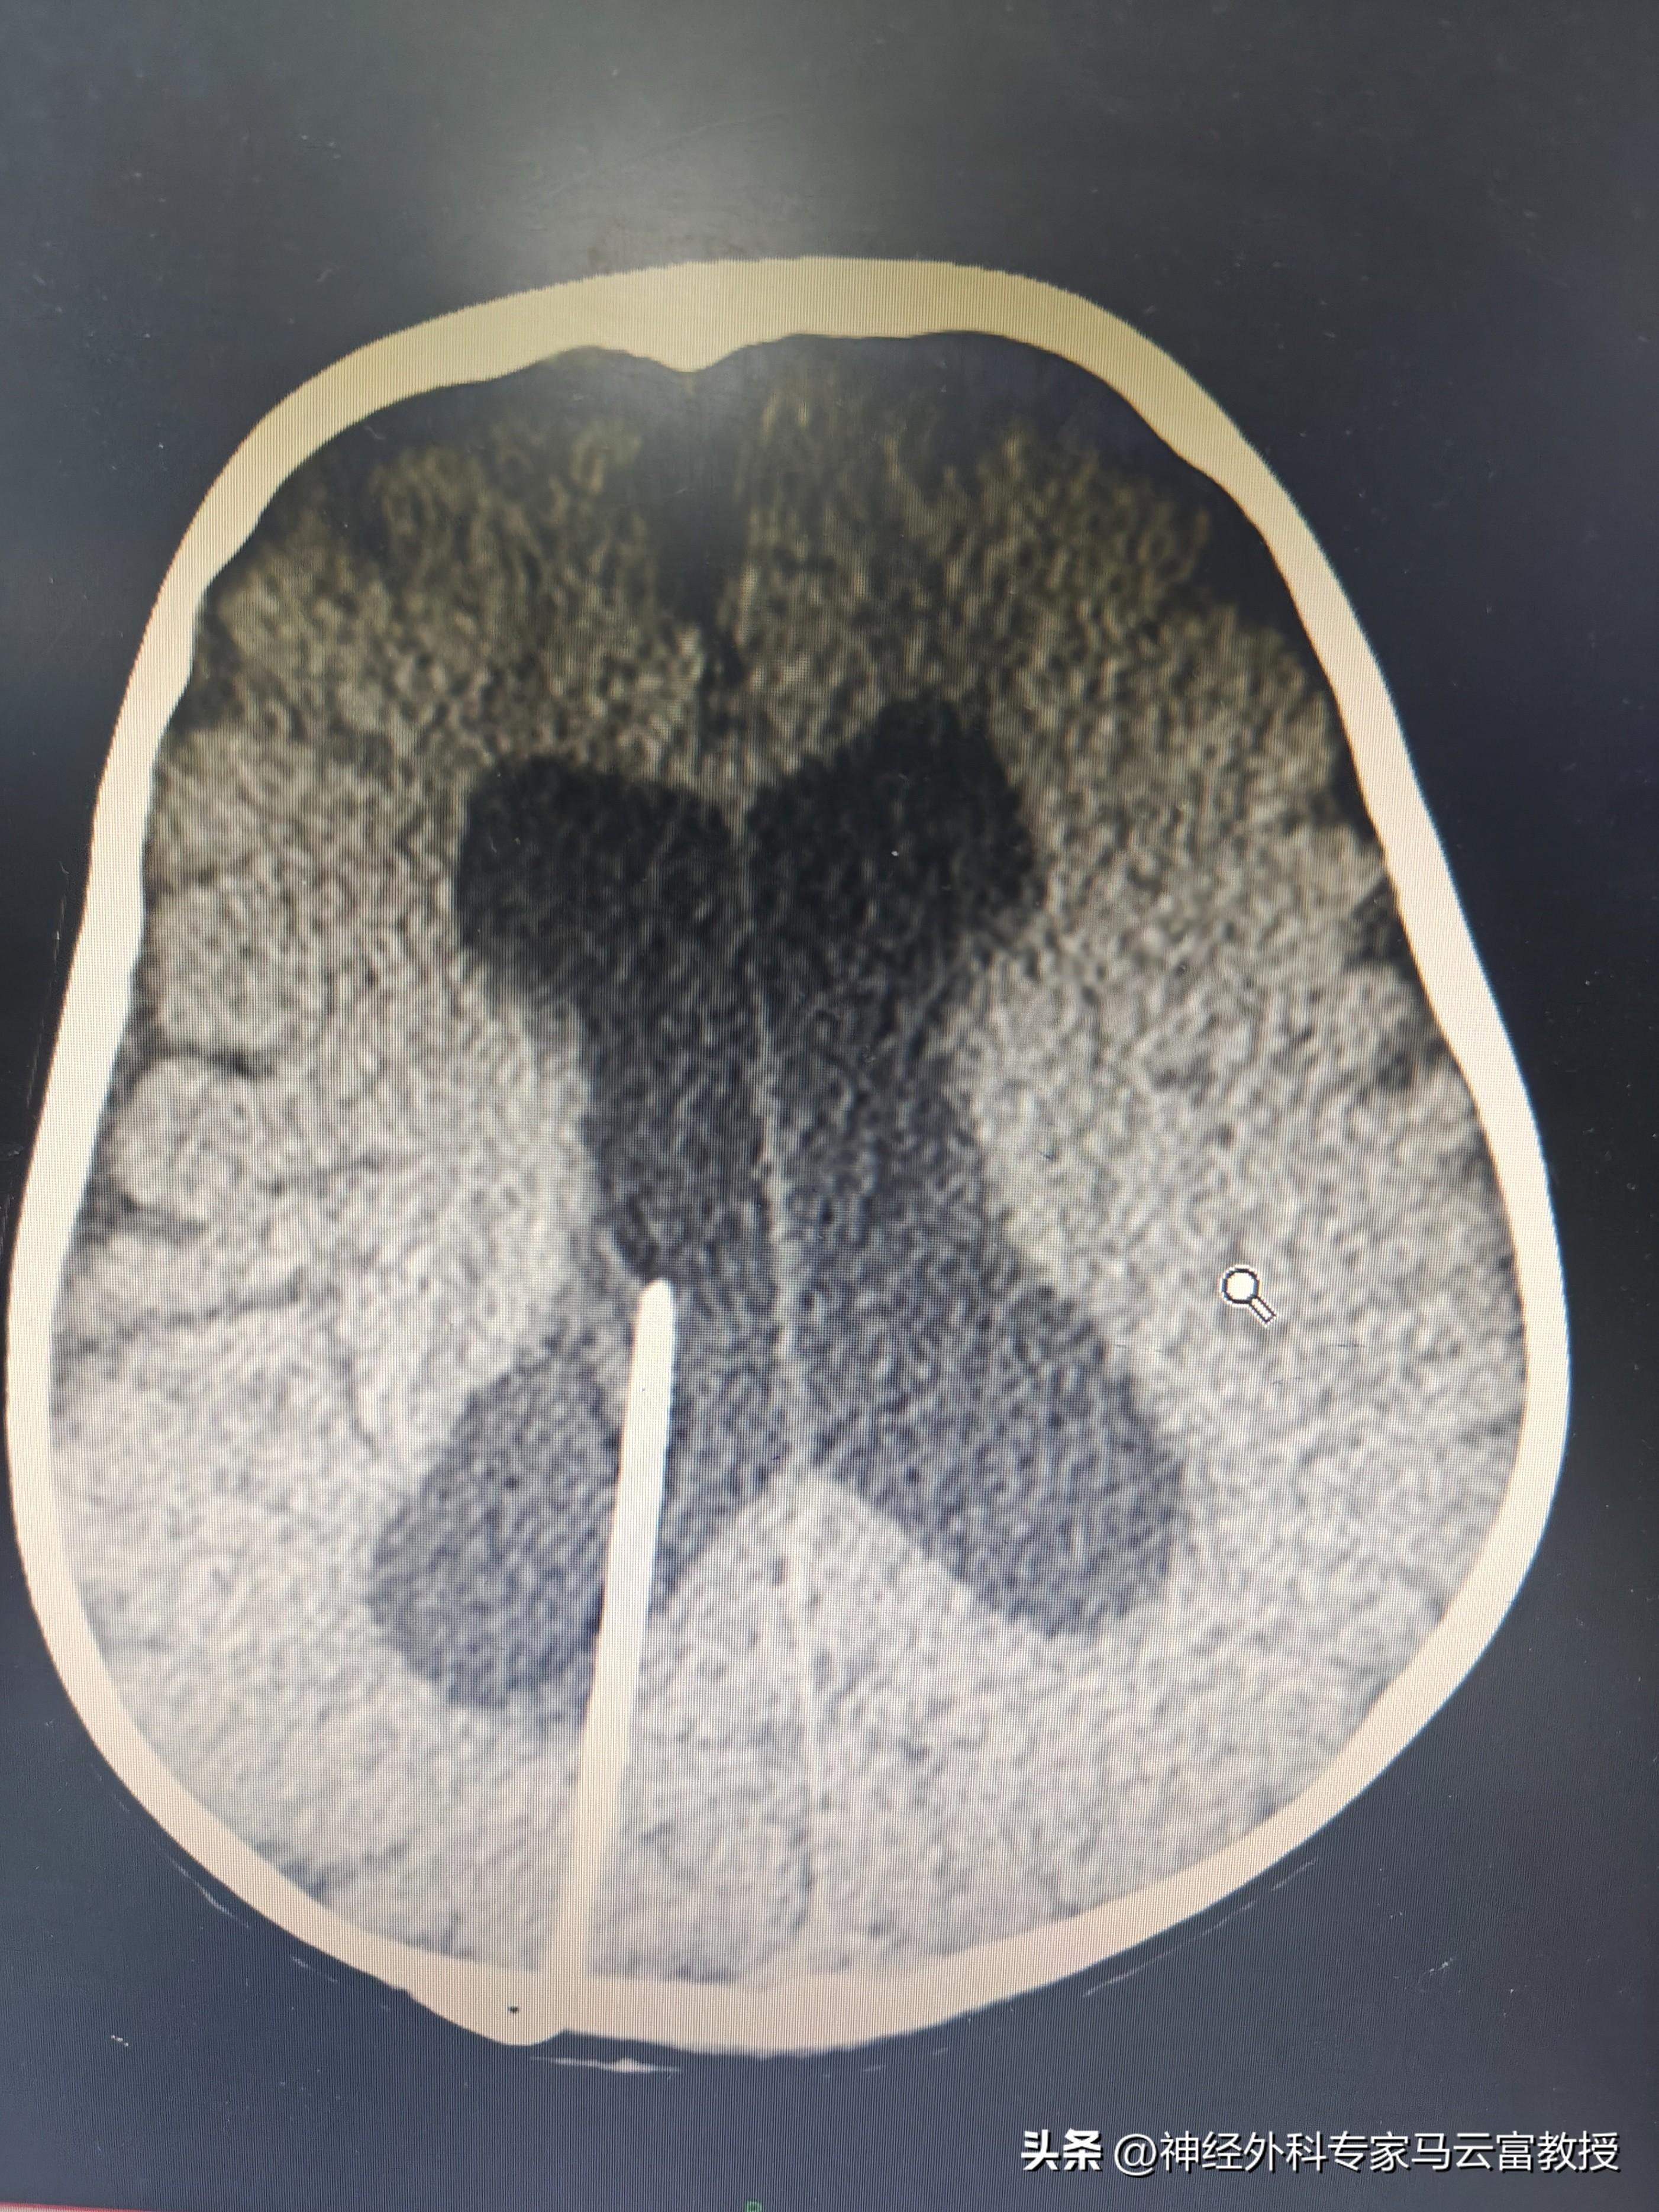

孩子頭圍已達57cm(遠超同齡正常水平),發育也明顯滯後,目前僅能發出 “爸爸”“媽媽” 的簡單音節。在當地醫院檢查時,醫生髮現寶寶側腦室正在逐漸增寬,建議立即轉診至我院進一步診治。

我院神經外科馬雲富主任接診後,通過細緻查體與顱腦 CT 檢查,明確診斷爲幕上腦積水。入院後,團隊完善了腦 MRI + 腦脊液電影成像等精準檢查,最終判斷爲不全梗阻性腦積水,且腰穿提示腦室內壓力不高。綜合評估後,馬雲富主任爲患兒制定了腦室 - 腹腔分流術的治療方案,爲寶寶的大腦 “減壓”,重啓正常發育的可能。